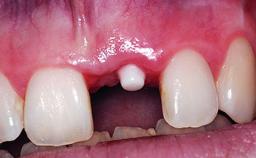

A 36-year-old male patient with a compromised maxillary central incisor was referred by his general dentist for consultation. The patient’s chief complaints were the gradual debonding of a temporary crown on the right central incisor and unsatisfactory esthetics due to an increasing diastema between the right central and lateral incisors. The patient reported a traumatic event some years previously, when a crown had been placed after root-canal treatment. The referring dentist wanted to provide a new crown restoration, but was concerned about the condition of the residual root. Anamnesis was negative for any other dental or periodontal pathology in the remaining dentition. The patient reported taking no medications: He was a smoker (10 to 15 cigs/day) and had realistic esthetic expectations.

Bone Augmentation Horizontal|Simultaneous|Staged

Soft Tissue Grafting Simultaneous

Bone Volume Deficient horizontally, requiring prior grafting